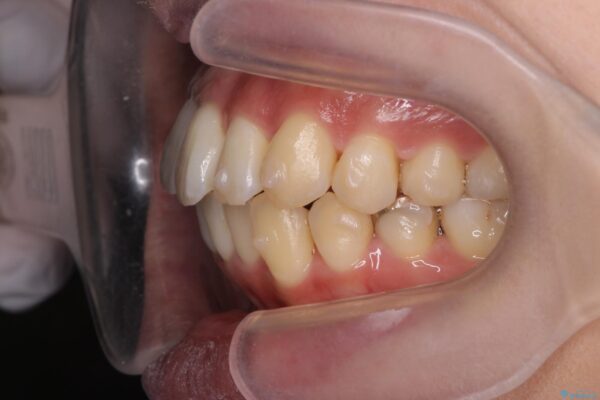

治療中

気になる犬歯のガタつきをマウスピース矯正で改善 治療中画像 気になる犬歯のガタつきをマウスピース矯正で改善 治療中画像 気になる犬歯のガタつきをマウスピース矯正で改善 治療中画像 気になる犬歯のガタつきをマウスピース矯正で改善 治療中画像